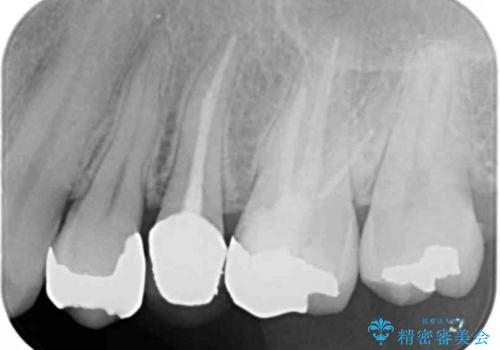

- 「笑った時に見えてしまう銀歯、古くなった修復物を白くきれいに治したい。」と希望され来院されました。

銀歯の下に再発していた虫歯を丁寧に取り除き、精密なセラミッククラウンで再治療を行います。

噛み合わせが強く、銀歯やクラウンは大きくする減ってしまっている状況でした。

噛み合わせをしっかり調整することで、安定した咬合関係を得ることができました。